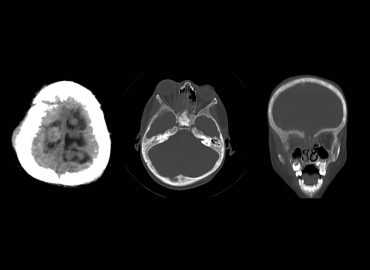

Hombre de 55 años, con antecedentes de cardiopatía y FA, consulta por sindrome convulsivo.